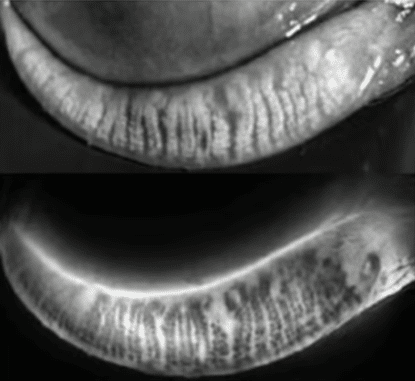

Le chalazion est une inflammation chronique d’une glande de Meibomius située à l’intérieur de la paupière.

Chaque paupière contient des glandes sébacées appelées glandes de Meibomius, qui participent à la production du film lacrymal en sécrétant une composante lipidique.

Lorsqu’une glande se bouche, le sébum s’accumule, provoquant une inflammation locale. Il en résulte une petite masse ronde sous la paupière, parfois accompagnée d’un gonflement ou d’une rougeur.